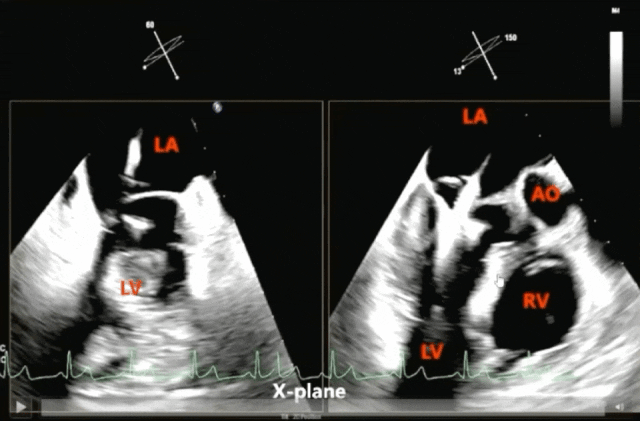

调整CDS(二尖瓣夹导管输送系统)蓝线和SGC蓝线对齐,把CDS缓慢送入SGC,在这个过程中,必须借助超声引导,以便清晰地观察到夹合器的整体形态,尤其是其前端与心房壁之间的位置关系。送入过程缓慢前行,到达左心房时,TEE指引将CDS送入左心房,直到SGC的末端标记位于CDS两个标记的中间骑跨(straddle)。

一旦夹合器弯向了二尖瓣,接下来调整夹合器的方向和位置。夹合器与二尖瓣环的位置有四要素:①夹合器要放置在反流最为严重的位置;②orientation,夹合器的定位必须准确;③trajectory,夹合器的行进轨道要设置正确;④alignment,夹合器夹壁方向须与瓣叶闭合的方向保持一致。

缓慢将夹合器送入左心室,确保夹合器不会出现向内侧或者外侧的偏向点头或者抬头运动,运动轨迹垂直于瓣环且平行于左心室长轴;对于交界或1、3区病变,夹合器两臂打开的角度不宜过大,一般在0°~60°进入,防止缠绕腱索;到达抓捕位置后,在3D影像上微调夹合器轴向;如需较大调整,将夹合器翻转后退回左心房重新调整方向和位置。